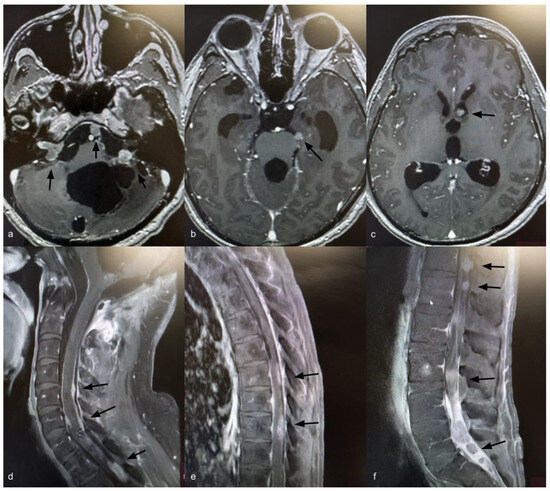

Fourteen years after the initial surgery, at age 40, the patient developed acute right-sided hearing loss. Brain and spinal MRI demonstrated multiple posterior fossa lesions, diffuse spinal leptomeningeal enhancement, and multiple solid lesions throughout the entire spine (Figure 3), consistent with LMD. Surgery was not pursued, as no clinical benefit was anticipated. The patient underwent craniospinal irradiation comprising 30 sessions. At the three-month follow-up, MRI showed stable disease. He subsequently developed symptomatic communicating hydrocephalus requiring ventriculoperitoneal shunt placement. CSF cytology was negative for neoplastic cells. Six months after radiotherapy, with no radiological improvement, systemic chemotherapy was initiated with carboplatin (600 mg), etoposide (175 mg), and vincristine (2 mg), administered every 28 days for six cycles. Thirty months after the diagnosis of LMD, the patient remains alive with stable brain and spinal lesions with no evidence of new disease (Figure 4).

Figure 3.

Axial T1-weighted brain MRI with gadolinium showing ventriculomegaly and multiple posterior fossa lesions at the right internal auditory canal, left cerebellopontine angle, prepontine cistern, and left frontal ventricular horn (a–c) (black arrows). Sagittal T1-weighted spine MRI with gadolinium showing leptomeningeal dissemination (d–f) (black arrows).